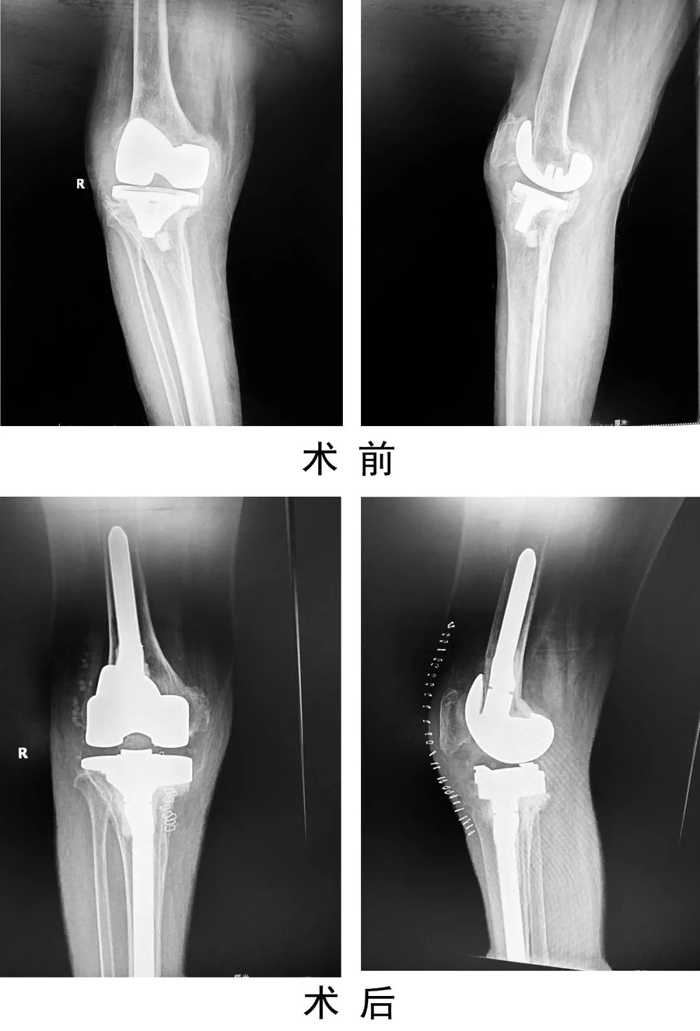

患者,女,69歲,因“右膝人工關(guān)節(jié)置換術(shù)后6年,疼痛伴活動受限1年”入住關(guān)節(jié)運動醫(yī)學(xué)二科。術(shù)前X線示右膝人工關(guān)節(jié)假體松動,感染指標檢查:C反應(yīng)蛋白80mg/L,血沉20mm/h,關(guān)節(jié)穿刺培養(yǎng)提示表皮葡萄球菌感染。查體見有膝部有一長約15cm手術(shù)疤痕,皮溫高,關(guān)節(jié)腫脹,右膝關(guān)節(jié)活動受限。入院診斷為:右膝關(guān)節(jié)假體周圍感染,人工假體松動,右脛骨平臺骨缺損。

患者入院后,關(guān)節(jié)運動醫(yī)學(xué)二科手術(shù)團隊制定嚴密的手術(shù)計劃,為患者實施了一期右膝人工關(guān)節(jié)翻修術(shù),一次手術(shù)清除原假體,徹底清創(chuàng)后,重新植入翻修假體。手術(shù)后患者右膝刀口一期愈合出院,患膝功能良好,疼痛緩解。復(fù)查感染指標C反應(yīng)蛋白4.45mg/L。